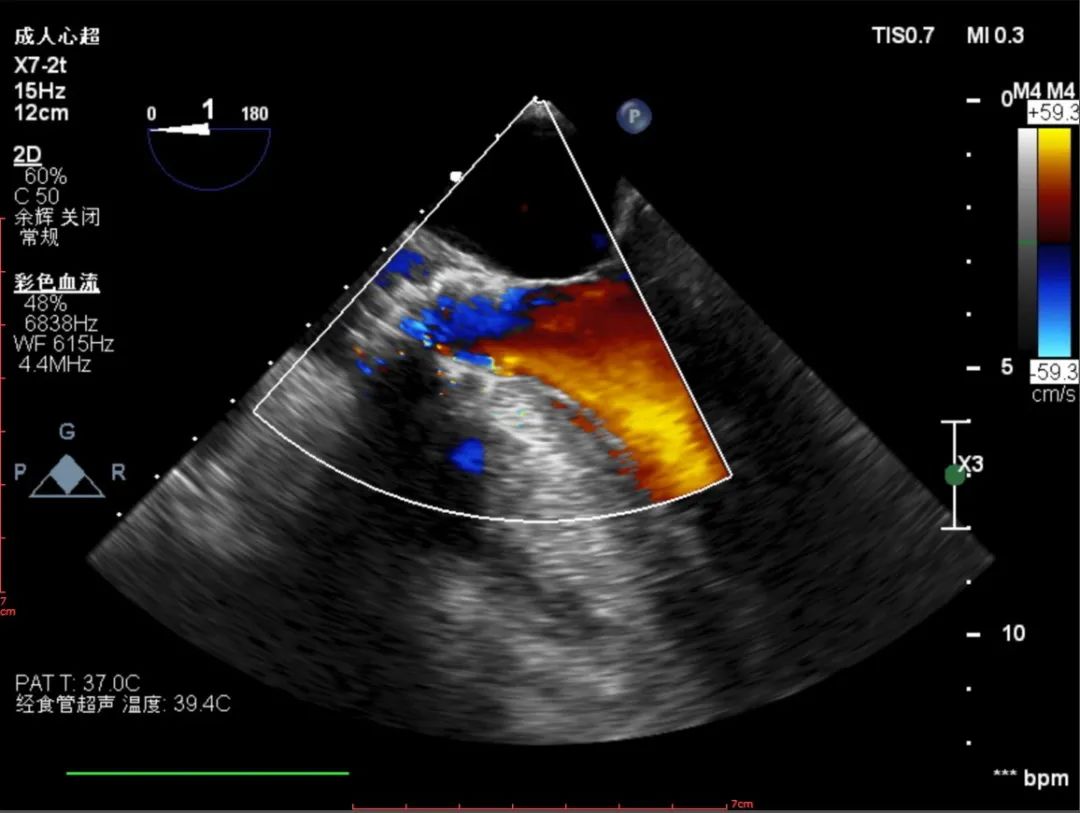

彩超评估:

超声下观察瓣膜展开形态可,血流动力学改善明显

跨瓣压差:

术前跨瓣压差126mmHg,植入后跨瓣压差12mmHg